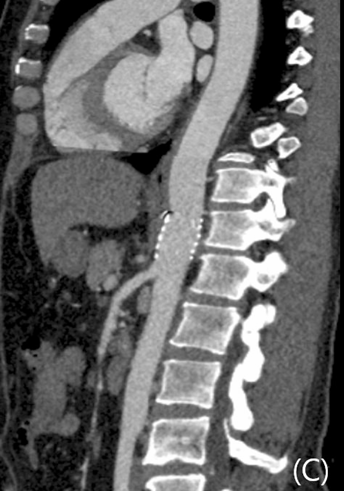

응급 지혈을 위한 스텐트-그래프트 설치술을 시행 받은 후 환자의 생체 징후는 안정화되었고, 후복강 혈종이 감소하는 양상으로 퇴원하였음. 시술 후 3개월 외래에서 시행한 경과 관찰 전산화단층활영에서 후복강의 혈종은 모두 없어졌으며 복강동맥으로의 혈류는 원활하였고 스텐트-그래프트는 상장간막동맥 바로 위에 잘 설치되었음이 확인됨(Fig. 5). 현재 3년째 외래 경과 관찰 중인 상태로 스텐트 확인을 위한 1년 주기의 전산화단층활영 검사와 정신과적 진료를 받고 있음.

Fig 5A

Follow up contrast-enhanced axial (A), coronal (B), curved MPR (C) CT scan after 3 months showed patency of celiac trunk and SMA. The ruptured pseudoaneurysm at the level of celiac trunk with hemoretroperitoneum was disappeared.

Fig 5B

Fig 5C